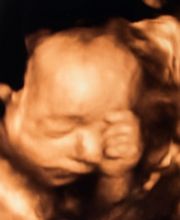

La Dott.ssa Susanne Pichl Mayr insieme alla figlia Dott.ssa Sandra Mayr hanno maturato molti anni di esperienza professionale combinata con conoscenze universitarie innovative e allavanguardia. Queste sono il connubio vincente che vogliono offrire alle loro pazienti. Si tratta, infatti, di un complemento ideale nel trattamento delle donne di tutte le età. "Ciò che ci sta particolarmente a cuore è prima di tutto ascoltare Voi come nostre pazienti, rispondere alle vostre domande, chiarire i vostri dubbi e trovare insieme a Voi la migliore terapia possibile." Lo studio medico è dotato di attrezzature all'avanguardia per eseguire ecografie durante la gravidanza, disponibile anche in 4D, ecografie ginecologiche, ecografie mammarie ed altri esami di alto livello. Questi sono i principali servizi: Ginecologia - Endocrinologia Ginecologica - Gravidanza - Salute del Seno - Screening per l'Osteoporosi - Urgenze - Interventi Chirurgici. Lo studio offre terapie chirurgiche in collaborazione con la Clinica Sant'Anna di Merano e la CityClinic di Bolzano.